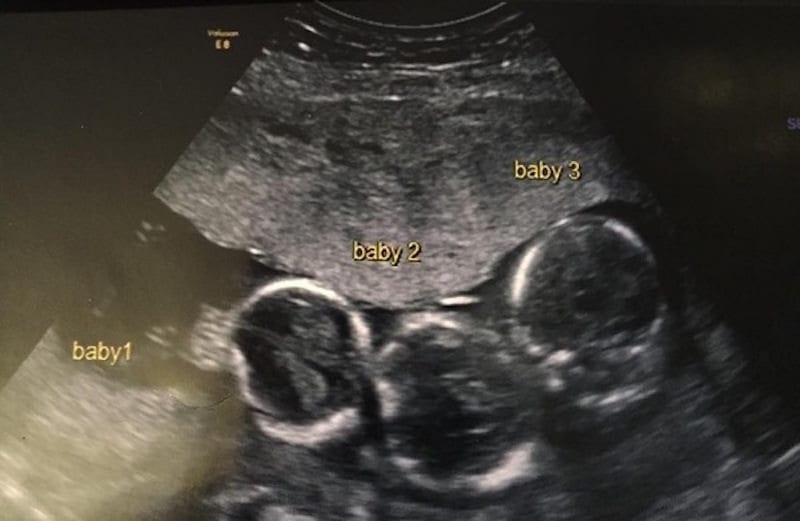

A Surprise Pregnancy

After getting an ultrasound, the couple nervously sat and waited for their results. What could it possibly show? Was Becki-Jo going to be okay? As it turns out, Becki-Jo and Liam were more than okay, they were expecting! As if in answer to their prayers, the couple found out that Becki-Jo was pregnant with triplets. How is that for expanding the family?

The Biggest Shock Of Becki-Jo’s Life

When Becki-Jo and Liam were notified of the news, they were quite clearly shocked. The symptoms that Becki-Jo had been displaying before the ultrasound were worrying, but after finding medical help they were able to move forward in a safe manner. With that being said, this isn’t where this extraordinary story ends.